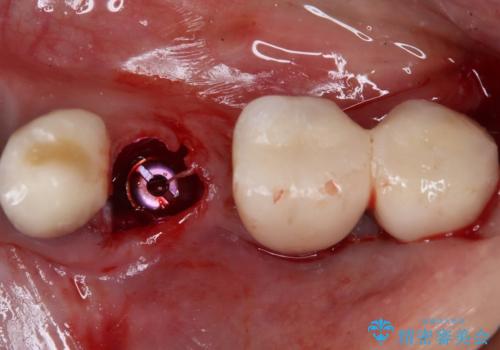

そのため、当院に新しく導入した手法により、抜歯をした日にインプラントを埋入し、そのままを仮歯を装着することで、他の歯への負担を軽減する計画を立てました。

インプラント埋入時に植立具合の安定性を測定したところ、十分な数値が得られたため、速やかに仮歯を装着して咬合回復をさせることができました。

抜歯を含めた外科処置を1回に抑えることができ、あっという間に治療を終えることができました。